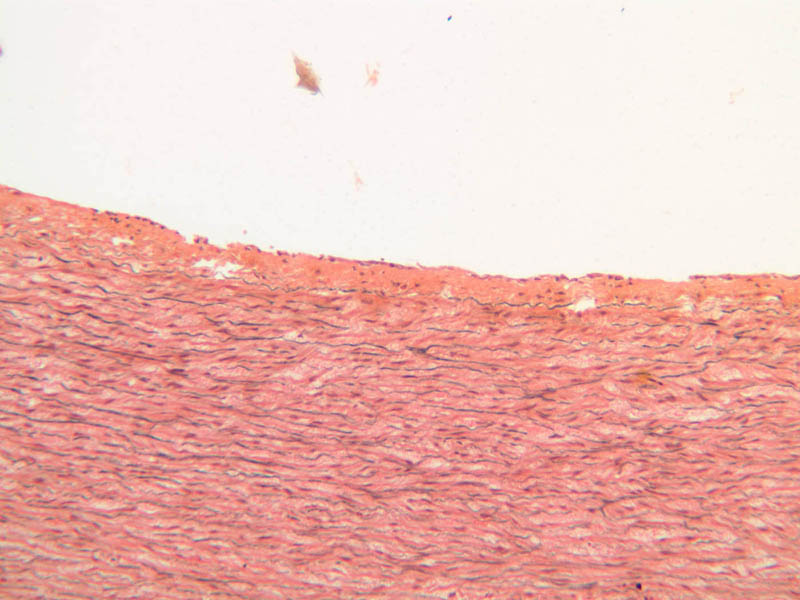

The blood is pumped from the heart into large, elastic (conduction) arteries. Examine a section of the aorta (A-26, H&E [2.5x, 10x, 20x, 40x-labeled] [2.5x, 10x-labeled, 20x, 40x]) which is a typical elastic artery. Although the tunica intima and tunica media are difficult to distinguish, note that together they are much thicker than the tunica adventitia. Using high power magnification, examine the tunica media and identify the cell types and fibers, recalling that elastic tissue appears light pink and refractive in H&E preparations. Compare this slide with a section of aorta stained to demonstrate elastic fibers (A-27, verhoeff [2.5x, 10x, 20x, 40x-labeled] [2.5x, 10x]).

Note how extensive the elastic tissue is in the tunica media. The elastic tissue is arranged in the form of numerous concentric elastic lamellae, which are cross connected by slender elastic fibers. Observe the distribution of elastic fibers in the tunica intima (A- 27 [2.5x, 10x, 20x, 40x]) and tunica adventitia (A-27 [10x, 20x, 40x]). The internal and external elastic membranes are not well demarcated in the aorta since so many elastic lamellae are present. The elasticity of the aorta allows it to expand and absorb much of the pressure during contraction of the left ventricle (i.e., systole). When the ventricle relaxes (diastole), the elastic aorta contracts, continuing the movement of blood into the medium and muscular arteries.